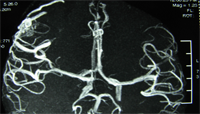

术前DSA检查及MRA检查见畸形血管团。